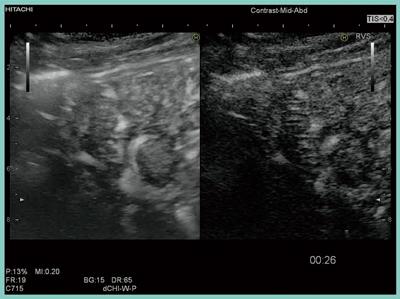

画質も優れており,Bモードでは約15cmの深さまで観察が可能である。10cmを超えると画像が流れはするものの,細い血管まで描出可能で,深部に非常に強い。造影超音波Kupffer相で肝癌の穿刺をすることが多いが,深部にフォーカスすることで高いコントラストが得られ,MI値を調節することで肝表面も明瞭に観察できる。Kupffer相における高音圧フラッシュの欠損像は,深部までしっかりと観察することができ(図4),Kupffer相でのストレスのない穿刺が行えると期待される。

図4 ソナゾイド造影超音波:Kupffer相

高齢で呼吸停止困難の症例を,各画素の最大輝度値をフレームごとに重畳表示をすることで造影剤の走行の視認性を改善するMicrobubble Trace Imaging(MTI)モードで観察した。画像が少し流れるものの,体動補正機能があるため,呼吸下であっても観察可能な画像を得られる(図5)。

図5 MTIモードの体動補正機能

小さな呼吸をしているにもかかわらず,重畳表示が得られている。